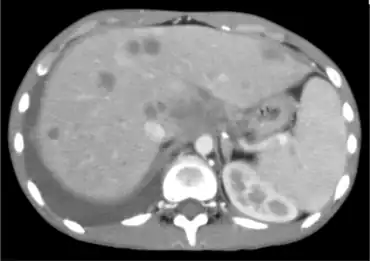

| Image with disseminated coccidioidomycosis | |